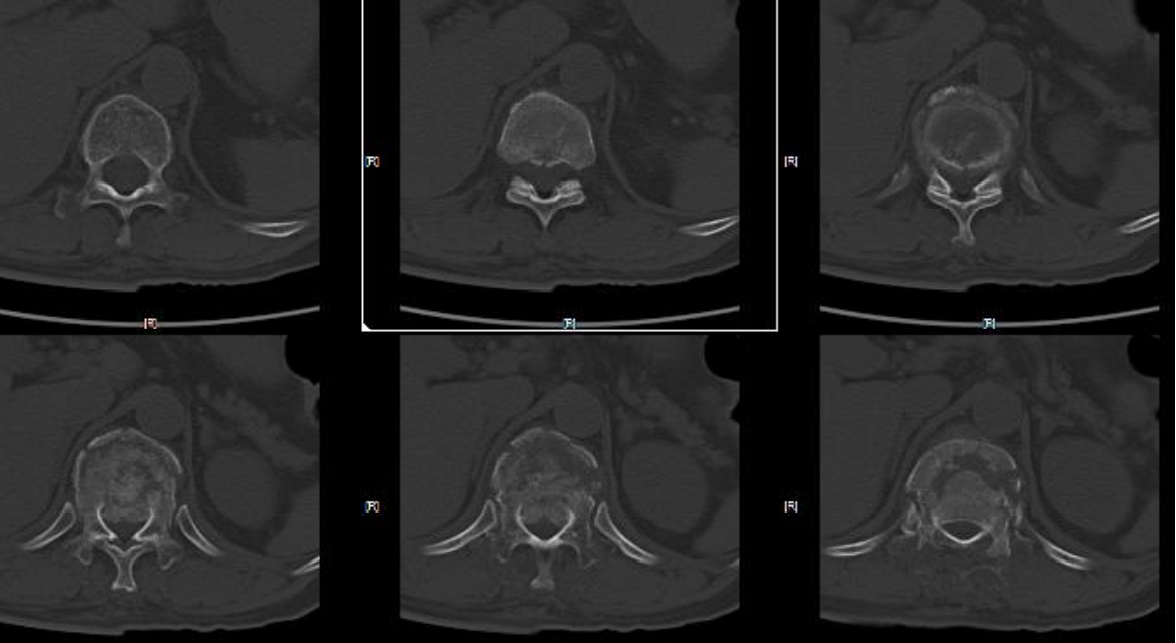

病例2车祸伤,完全性脊髓损伤

AO分型

- 分型:T12L1 C型;T12 B2型,L1 A1型

- 神经功能障碍分级:N4

- 修正参数:

- AO补充评分:C+N3(8+4) 12分

TLICS评分

- 骨折脱位(3分)

- 完全性神经损伤 (2分)

- PLC断裂(3分)

- 8分

载荷评分

- 碎裂大于60% 3分

- 后凸4~9度 2分

- 移位大于50% 3分

- 8分,合并脱位

治疗方案:手术治疗;后路手术,长节段固定